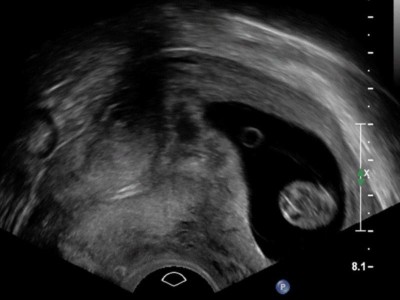

Akuter Harnverhalt in der Frühschwangerschaft

Eine 41-jährige III-Gravida I‑Para – Zustand nach Sectio – stellt sich mit Unterbauchschmerzen und tropfenweiser Harninkontinenz in der 11. Schwangerschaftswoche vor. Es besteht keine vaginale Blutung, gastroenterologische Ursachen sind ausgeschlossen. Was war der Grund für die Beschwerden?

Uterosakralligamente /© T. Fink, Chirurgin und Assistentin bei OP/© Georgiy / stock.adobe.com (Symbolbild mit Fotomodellen), Intrauterinpessar aus Kupfer/© Lalocracio / Getty Images / iStock (Symbolbild mit Fotomodell), Gynäkologische Untersuchung mit Spekulum/© Nomad_Soul / Stock.adobe.com (Symbolbild mit Fotomodellen), Intrauterinpessar/© JPC-PROD / stock.adobe.com (Symbolbild mit Fotomodell), Junge Frau sitzt auf Toilette/© Dragana Gordic / stock.adobe.com (Symbolbild mit Fotomodell), Laparoskopischer Eingriff/© RFBSIP / stock.adobe.com (Symbolbild mit Fotomodellen), Netz und Skalpell/© Beate Panosch / stock.adobe.com, Ärztin zeigt auf Modell eines weiblichen Beckens/© H_Ko / Stock.adobe.com (Symbolbild mit Fotomodell), Frau mit Balsenschwäche/© grinvalds / Getty Images / iStock (Symbolbild mit Fotomodell), Beckenbodentraining/© Mathias Ernert, Atelier Gesundheit, Schwangere macht Gymnastik/© fotostorm / Getty Images / iStock (Symbolbild mit Fotomodell), Transvaginalsonographie in der 11+1SSW/© Springer Medizin, Modell einer Levatoravulsion/© Baeßler K et al. / all rights reserved Springer Medizin Verlag GmbH, Magnetresonanz-Defäkographie des Rektums/© Deniz M, Kornmann M / all rights reserved Springer Medizin Verlag GmbH, Ältere Frau mit Trainerin beim Sport/© jacoblund / Getty Images / iStock (Symbolbild mit Fotomodellen), Laparoskopische Operation/© Iryna / stock.adobe.com (Symbolbild mit Fotomodellen), rotatorischer Descensus urethrae mit einem Meatus urethrae internus/© Anzböck T, Koensgen D: doi.org/10.1007/s00117-023-01215-7 unter CC-BY 4.0, Search Icon, Paar schaut glücklich auf Schwangerschaftstest/© Andrii Zastrozhnov / Stock.adobe.com (Symbolbild mit Fotomodellen), ZFA TALKS - Depression/© (M) seb_ra / Getty Images / iStock (Symbolbild mit Fotomodell) Logo: Springer Medizin Verlag GmbH, Ältere Frau fasst sich an die Brust/© Jelena Stanojkovic / Stock.adobe.com (Symbolbild mit Fotomodell), Person setzt DNS-Probe in Maschine ein/© Vit Kovalcik / stock.adobe.com